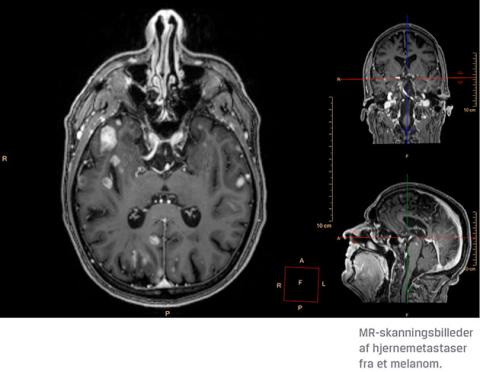

Forskningen inden for immunterapi og targeteret behandling er i rivende udvikling, og ikke mindst inden for melanombehandlingen er der optimisme. I 2017 registrerede man i Danmark 2.734 patienter med et eller flere invasive melanomer [1]. Til sammenligning registrerede man i 2016 2.888 patienter med invasive melanomer, hvoraf 414 fik metastatisk sygdom [2]. Blandt patienter med metastatisk sygdom sker der spredning til hjernen i mere end hvert tredje tilfælde, hvilket forringer prognosen betragteligt. Medianoverlevelsen herefter er 4-6 måneder [3].